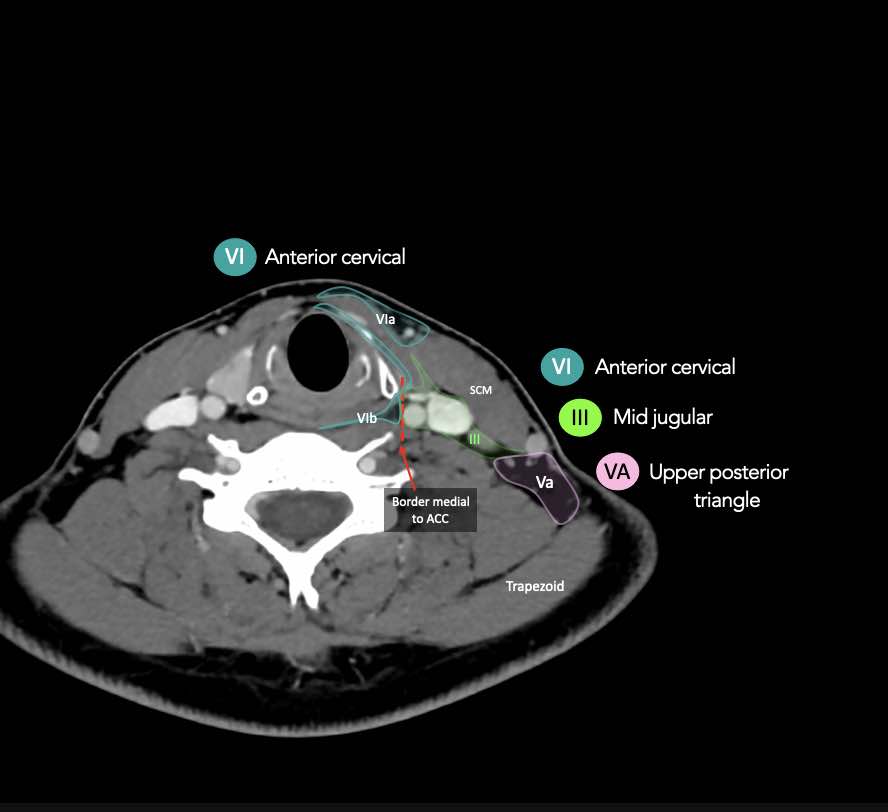

CT Scan Mặt Cắt Ngang (Axial CT)

Các lát cắt CT mặt phẳng ngang tương ứng với hình minh họa tổng quan.

Các lát cắt CT mặt phẳng ngang với hình ảnh chi tiết hơn.

Nhấp vào hình ảnh để phóng to.

VI – Cổ trước

Tầng này chứa các hạch tĩnh mạch cảnh trước nông (tầng VIa) và các hạch sâu hơn bao gồm hạch trước thanh quản, trước khí quản, cạnh khí quản và hạch thần kinh thanh quản quặt ngược (tầng VIb).